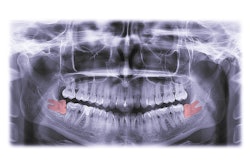

The prophylactic extraction of mandibular third molars is a controversial topic in orthodontics, with significant variability in clinical decision-making. This study aimed to explore the factors influencing such extractions among orthodontists in Israel, they wrote.

Impaction characteristics (35.2%) were the most frequently considered factor for prophylactic extraction followed by mandibular arch crowding (26.1%), with only 4.5% routinely referring patients for extraction.